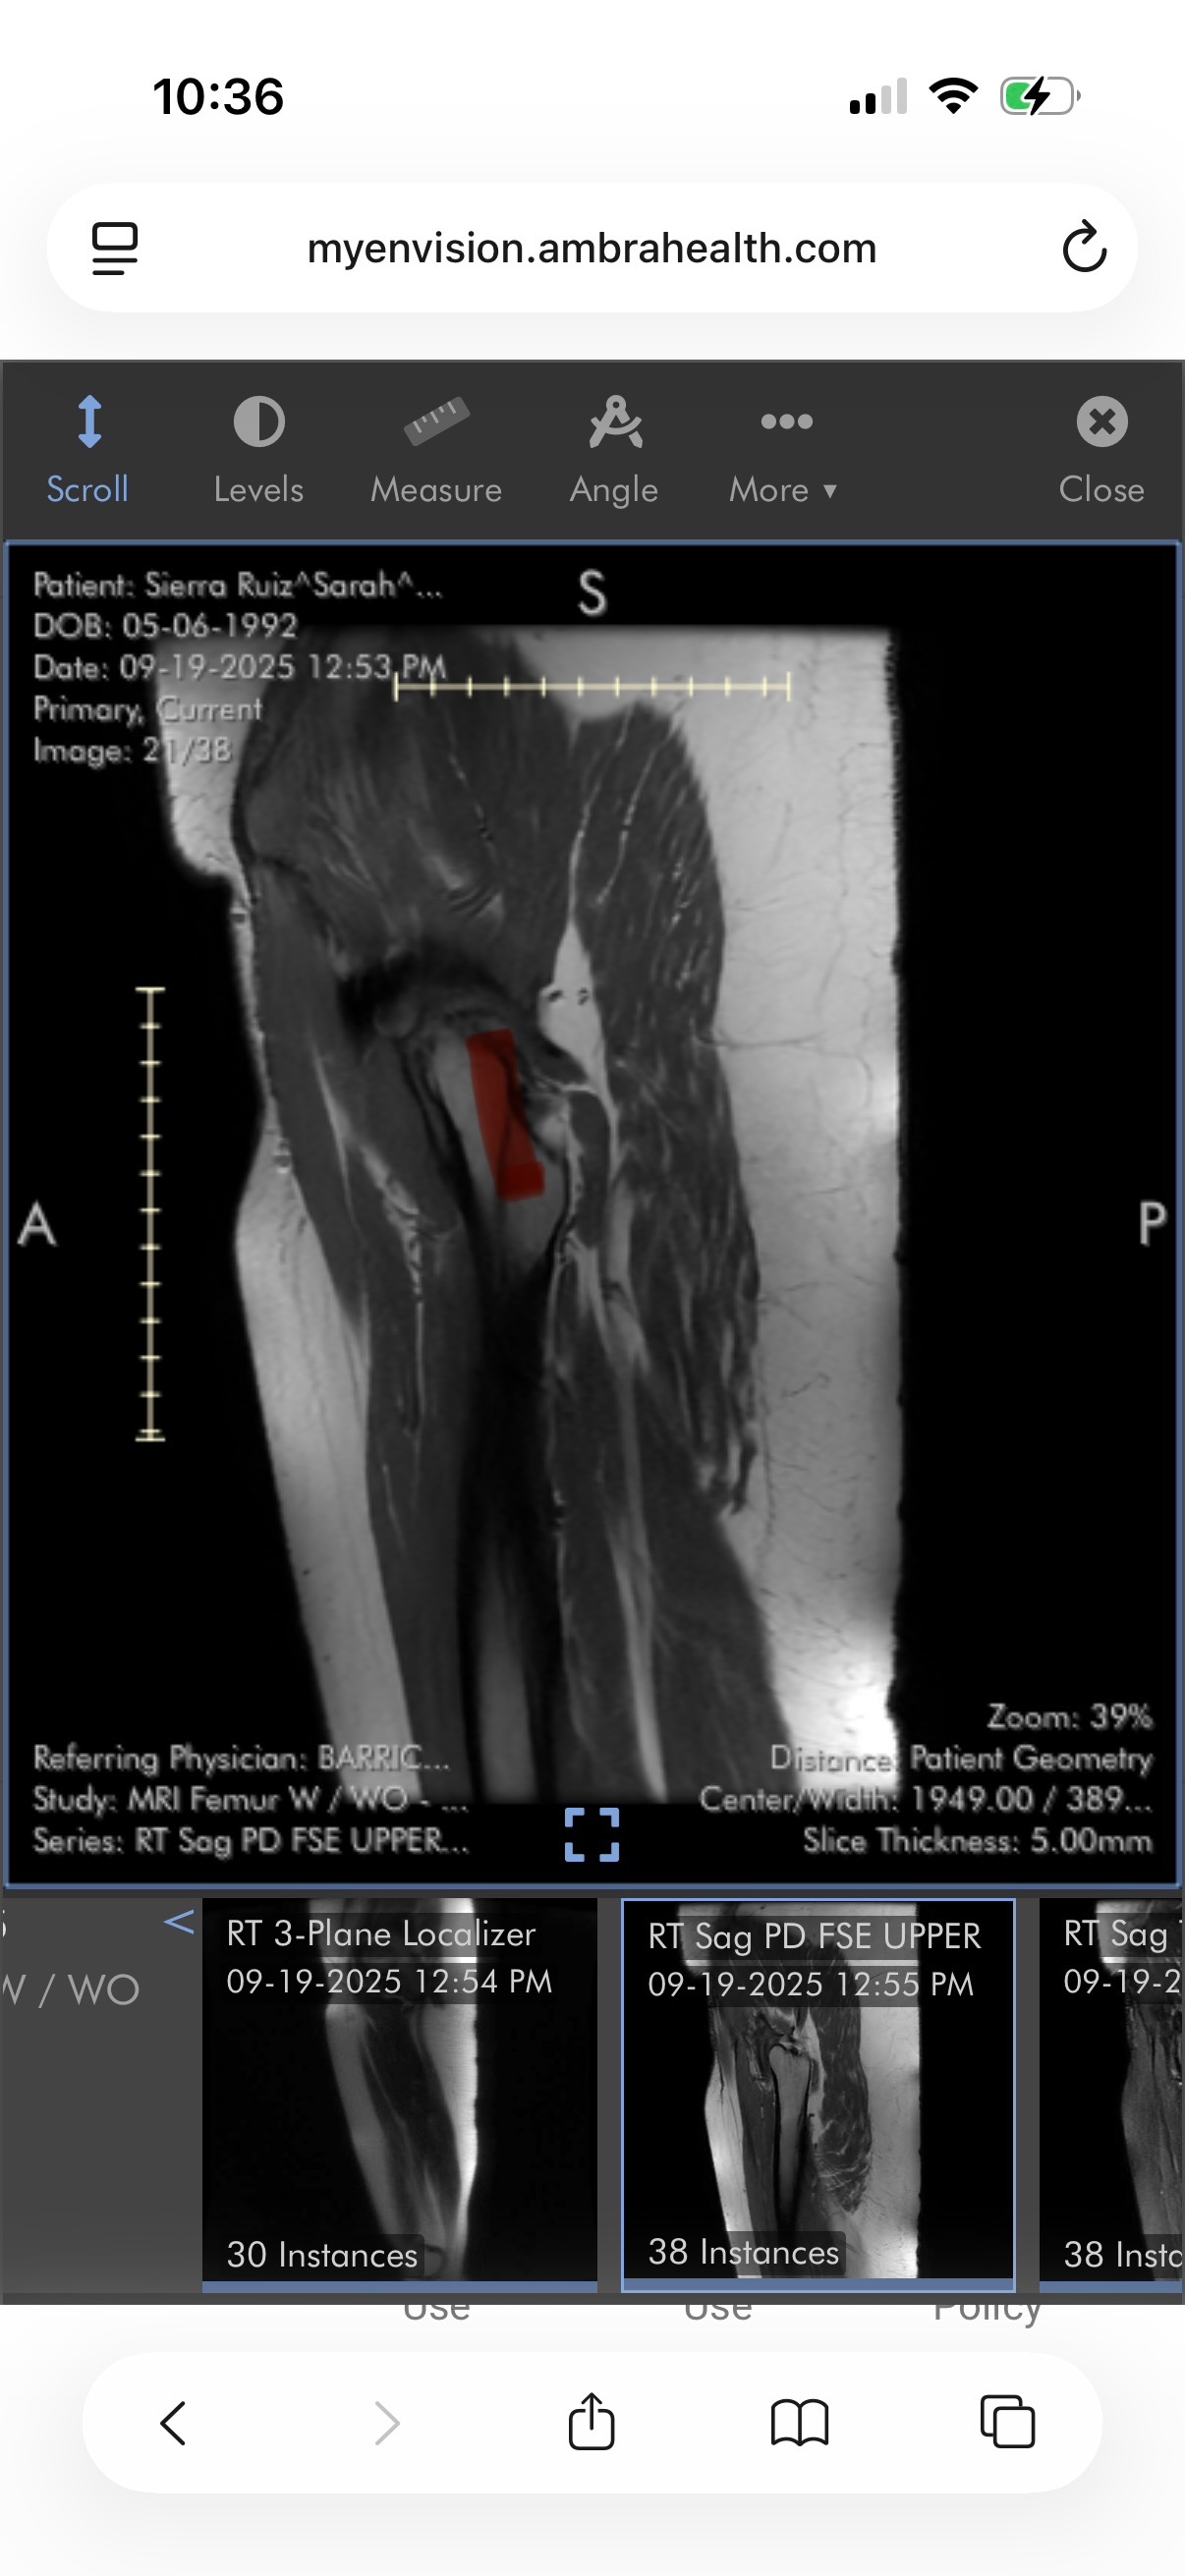

They’re planning to do an aspiration to confirm what they believe is a deep infection. From there, they’re likely placing a surgical antibiotic delivery system directly into my body. And that’s just the beginning. We’ll need to travel again for whatever surgery comes next—but this time, it will be with some of the best doctors in the world, and for the first time, I feel like someone is going to truly fight to save me. Between everything with my leg, and the lupus and scleroderma I feel like I’m falling apart.

On 3/27 Sarah went in for a procedure to aspirate the fluid from her hip and have a new drain placed. Not that it is surprising, but they did not place the drain like they were supposed to. The purpose of the drain is for Sarah to receive antibiotics and sclerotherapy through it, as well as to keep the fluid from reaccumulating over and over like it has been. This is not guaranteed to work, but it is the last resort before we have to have another open debridement.

The fluid has already come back worse than it was before. To top it off, her trauma surgeon told her there was nothing further he could do to help her at this time. He destroyed my wife's leg and left her suffering, with no solution, no pain management, and no trust left in her doctors.